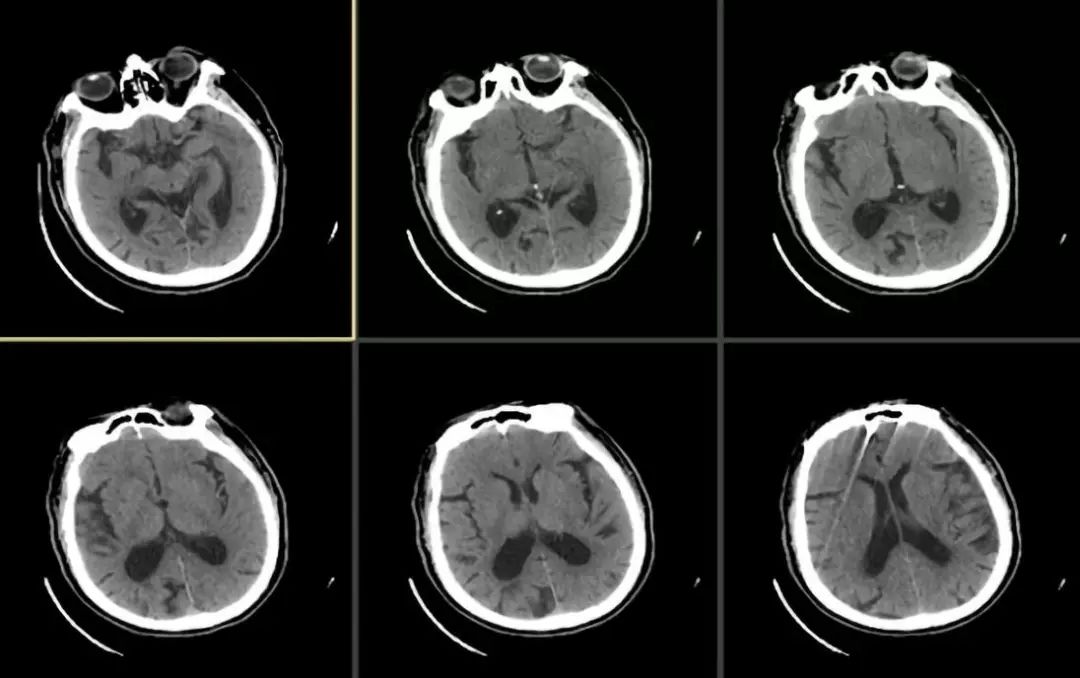

溶栓后复查头颅CT检查未见出血,但左侧大脑中动脉有高密度征(图2)。

图2

患者溶栓前症状较轻,予以阿替普酶溶栓治疗后症状加重,复查头颅平扫CT未见出血,左侧大脑中动脉有高密度征,考虑有急性大动脉闭塞,向家属交待病情后,家属表示知情同意行全脑血管造影,如有大动脉闭塞,即时予以血管内取栓治疗。